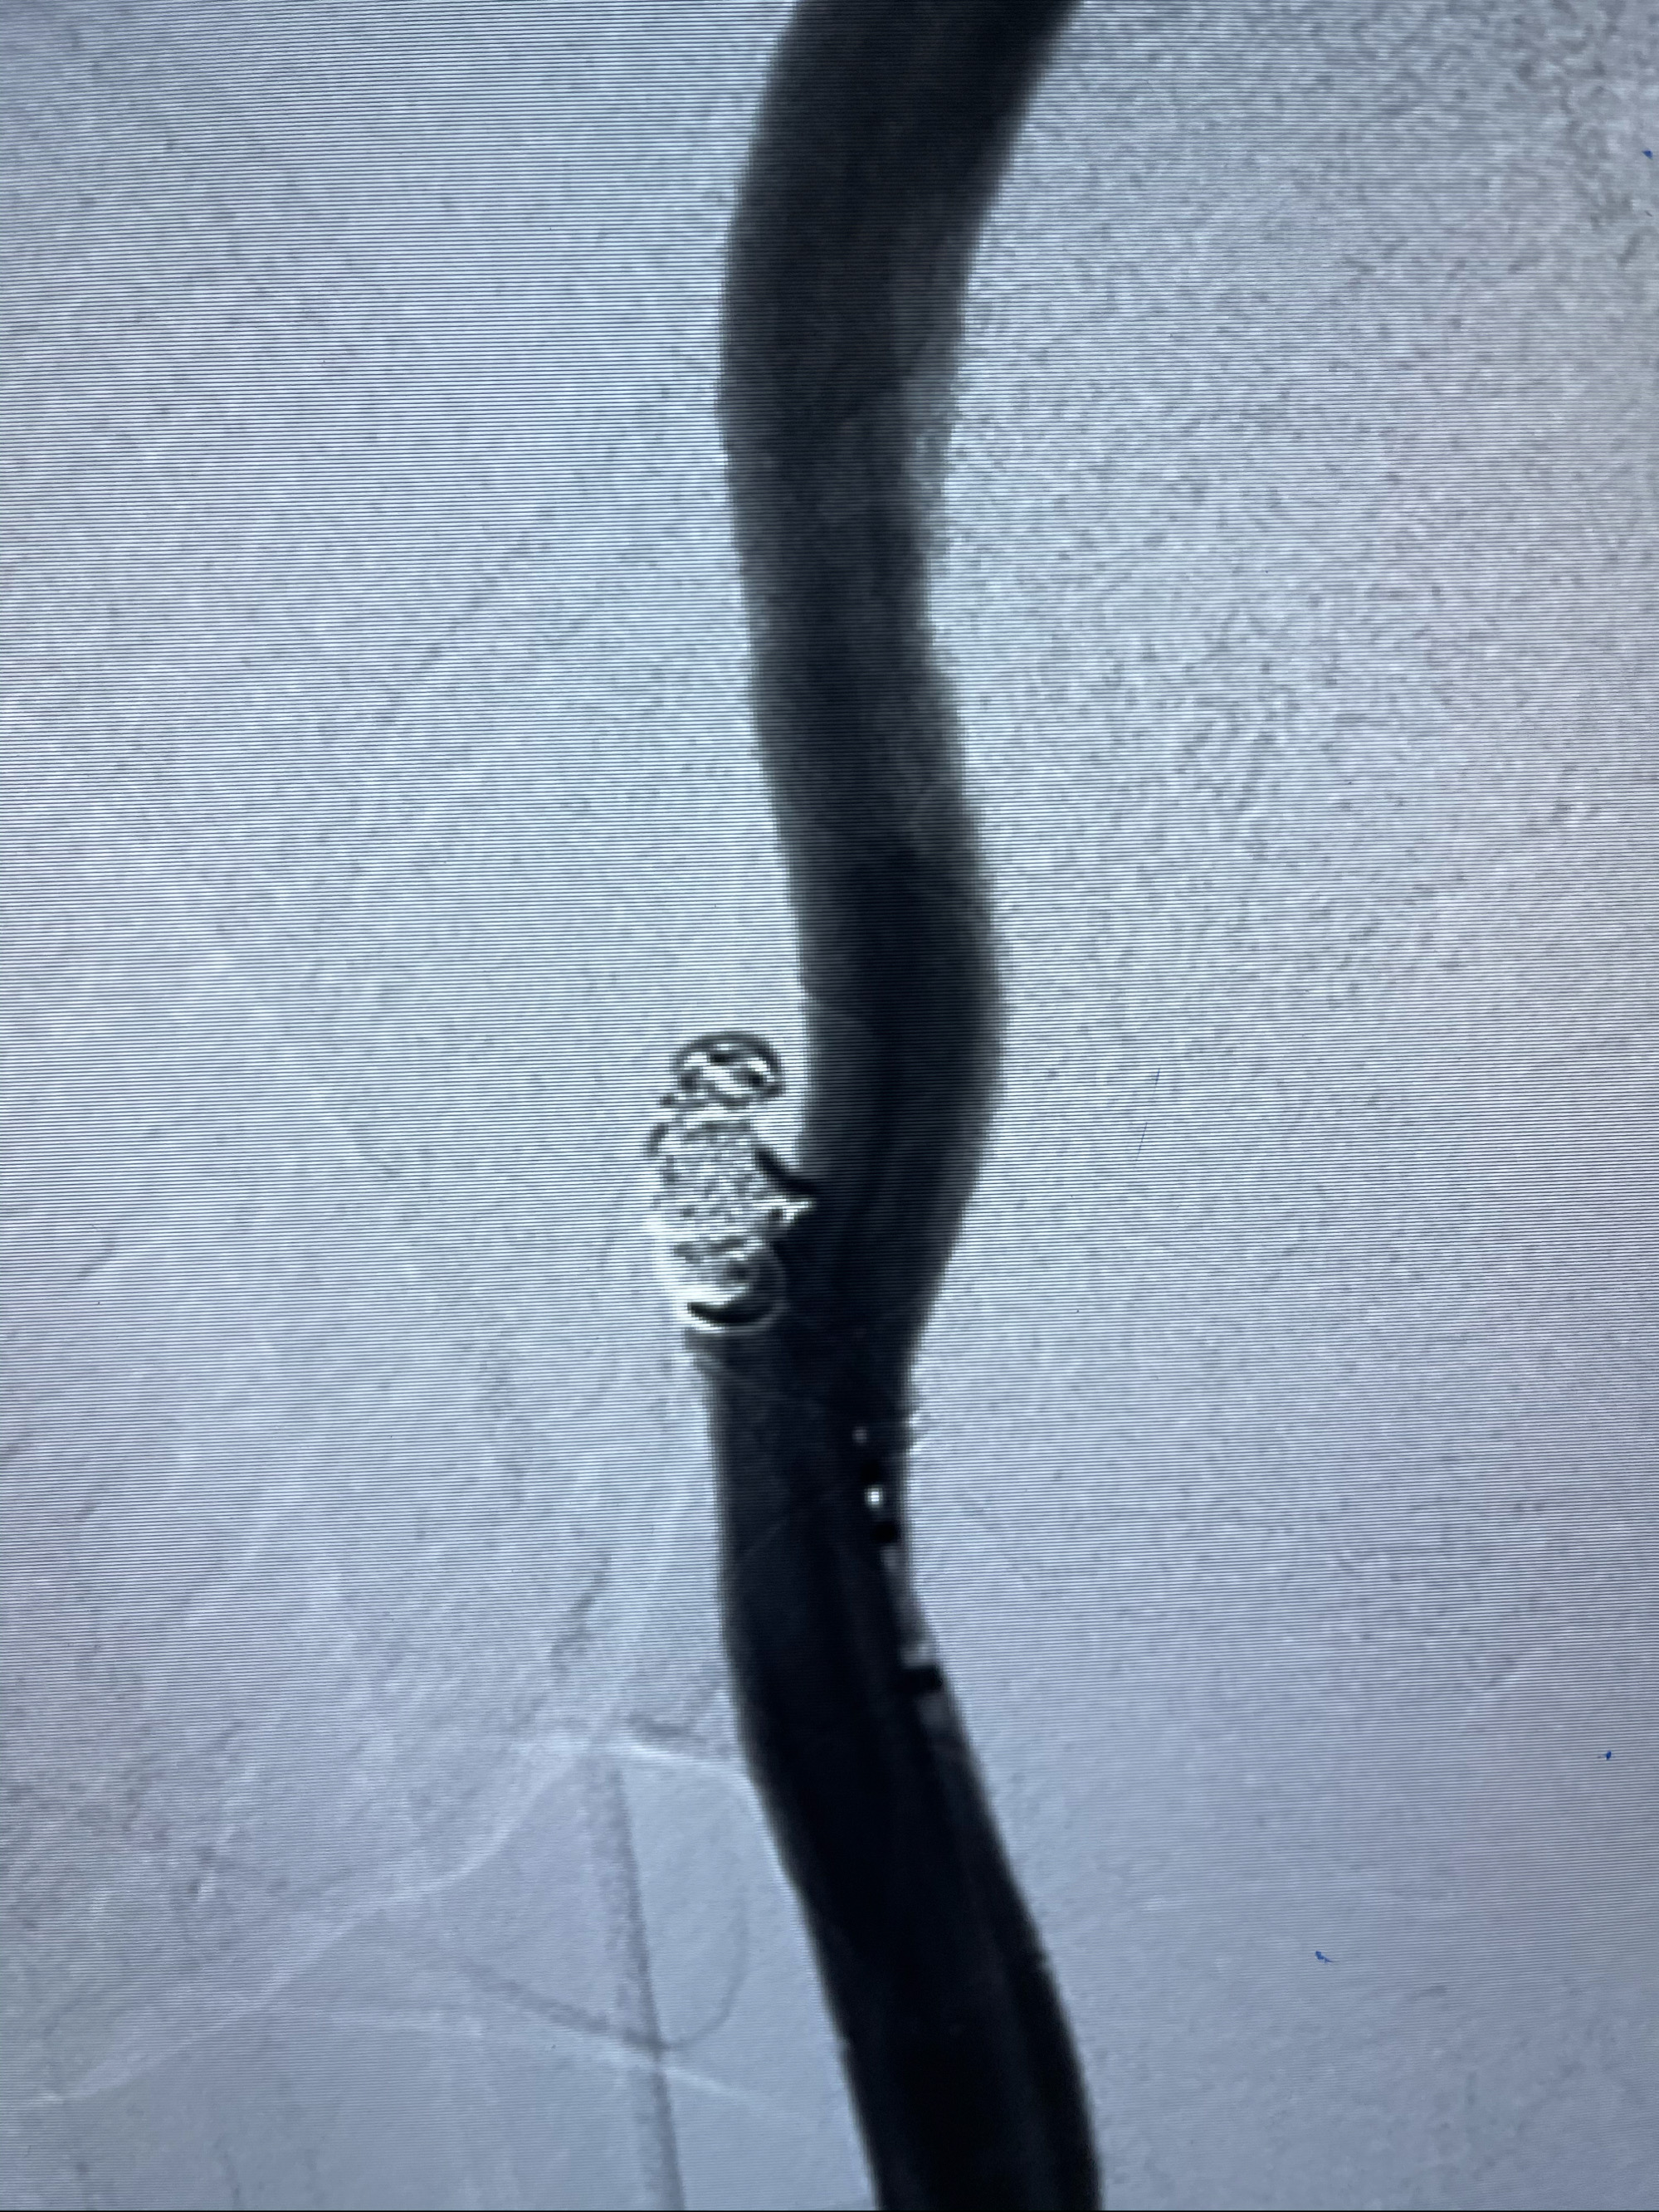

支架到位

支架释放,透视下